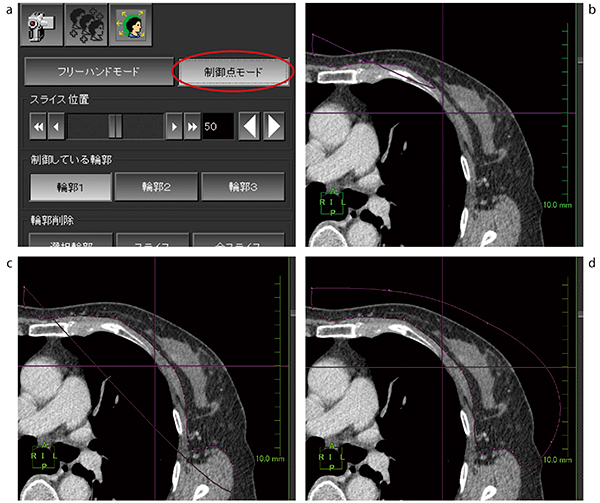

実際にMIP画像を作成する場合,骨や筋肉が腫瘍と重なるため,それぞれのボリュームを分ける必要がある。しかし,通称“骨抜き”と呼ばれるWLを上下させて対象ボリュームの選択消去や選択抽出などを繰り返す方法では,このような淡い造影効果のボリュームを分けることは難しい。特に,乳腺については筋肉と腫瘍のCT値が近接してしまうケースがあることや,乳房サイズが小さい場合には筋肉と腫瘍が距離的に近接することから,その切り分けが難しくなる。そのため,われわれは症例によってセミオート抽出法の“制御点モード”と呼ばれる標準機能を用いて作成を行っている(図1 a)。

秀逸な操作性の制御点モード

セミオート抽出法は,スライスごとにオペレータがフリーの形でボリュームを選択できる操作であるが,風神でのこの操作性を当院では非常に高く評価している。Adobe Photoshopなどの汎用イメージ編集ソフトウェアなどでもそうだが,マウス操作でフリーハンドに図形を描く場合,直線で図形を描出することは容易ではあるが,曲線を伴う描出の際は操作にかなりの慣れが必要であると考える。しかし,風神の制御点モードは,点をプロットすることにより描画する手法である。このプロット手法では,Microsoft PowerPointで描くようなイメージで曲線の描画が可能である。乳房はその構造上,曲線を描く部分が多く含まれるため,この手法による領域選択は非常に有効であると考えている(図1 b〜d)。

描画は各スライスすべてを描く必要はなく,数スライスを選択して描く。これは各スライス間でそれぞれに補間されるためである。また,プロットの失敗の際は右クリック一つでUNDO操作となるので,プロットミスも瞬時に元に戻すことができる。描いた後から修正が必要と判断された時には,プロット点の位置を個々に修正可能である。これらの手法が非常に有効なことから,幸いこの画像処理に関する作業は10分程度で処理することが可能となっている。

図1 セミオート抽出法の制御点モード

a:制御点モード選択

b:任意の位置からプロットを開始

c:数点のプロットを追加する。

d:滑らかな曲線を描くことができる。